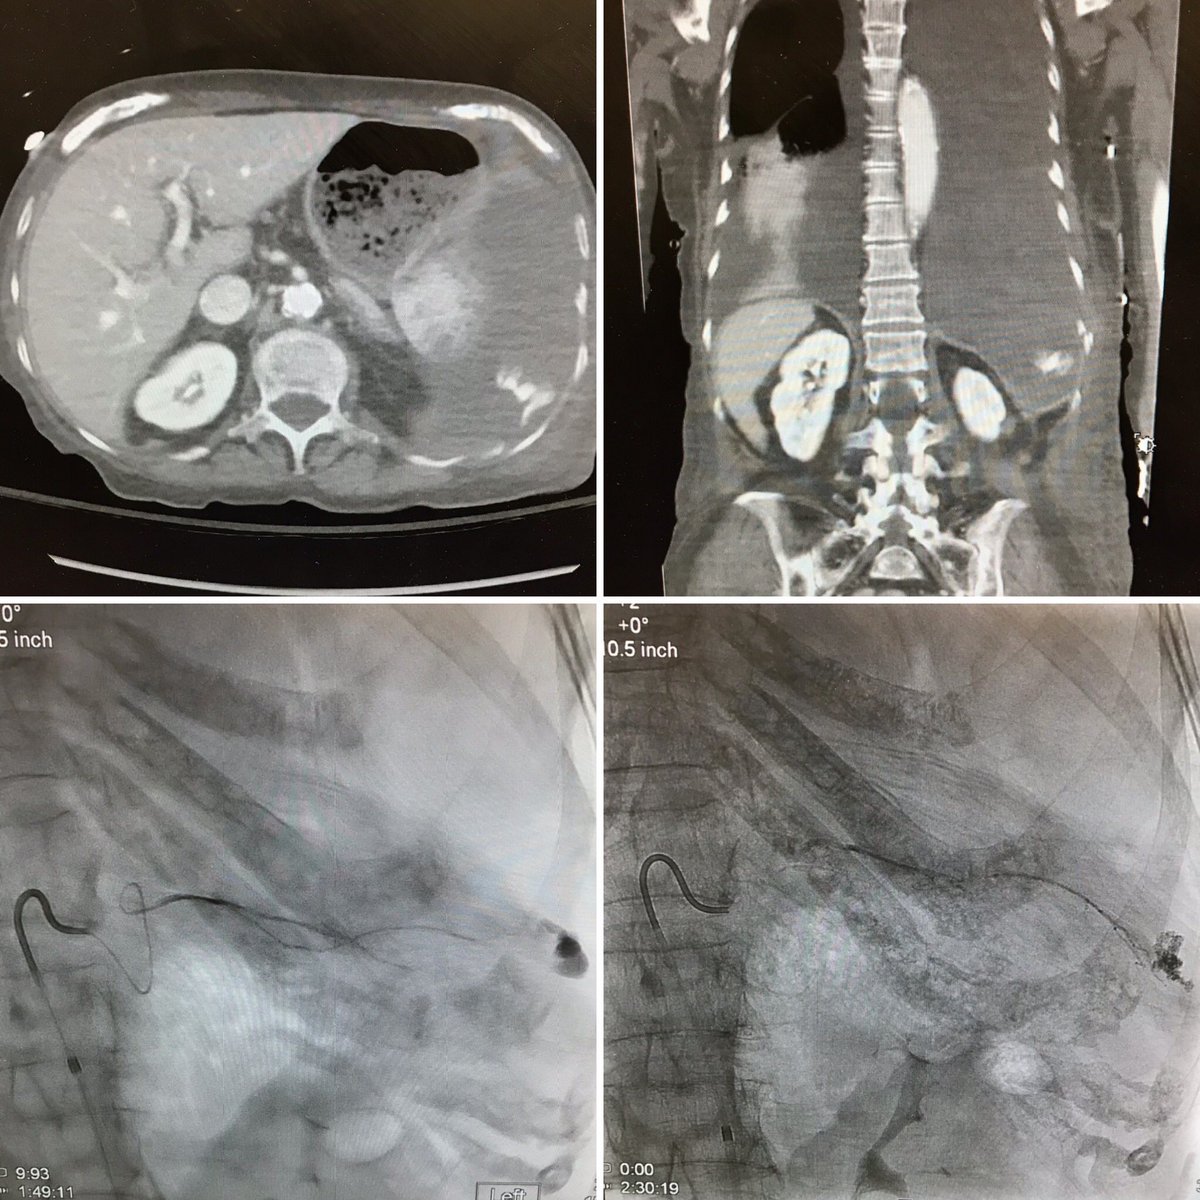

@Brown_VIR Glad we could #JustGlueIt on our last case together! Honestly, I’ve been overwhelmed by the well wishes over the past few weeks. Thank you from the bottom of my heart to everyone @Brown_VIR. It’s been a blast working with @brownradres, and excited to return to @MountSinaiIR.